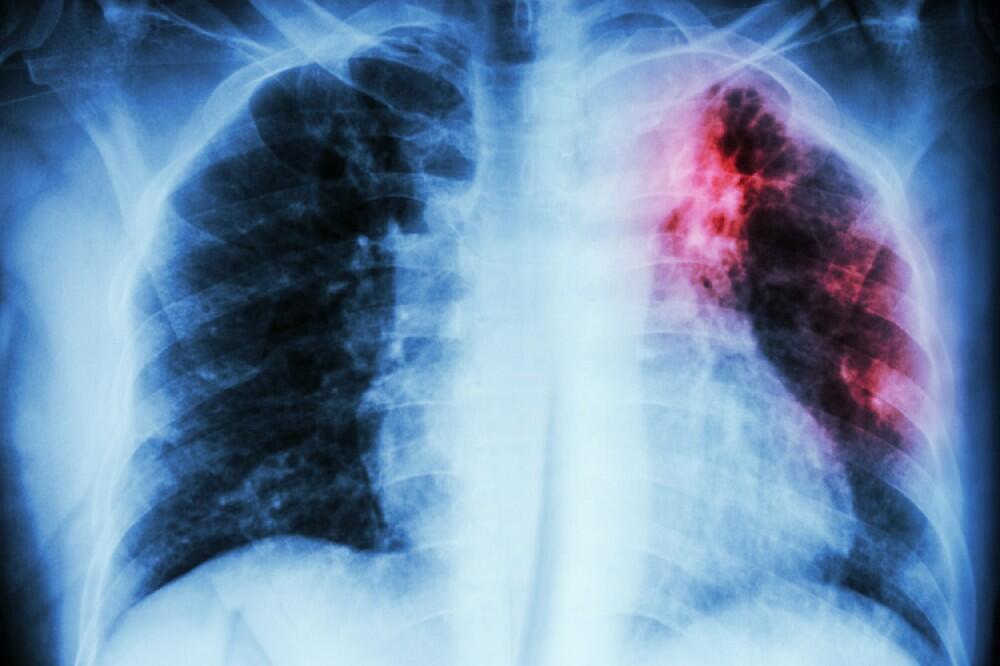

Azərbaycanda vərəmlə xəstələnmə dinamikası (100.000 əhaliyə): 2015 ildə bu göstərici 41.1 olan halda, 2025 ildə - 21,5 qeyd olunub.

Azərbaycanda ilkin ağciyər vərəmli xəstələr arasında TDM-nin (Turşuya Davamlı Mikobakteriya - Vərəm Mikobakteriyası) aşkar olunması dinamikası 2015 ildə 53% olduğu halda, 2025 ildə bu göstərici 86% çatıb.